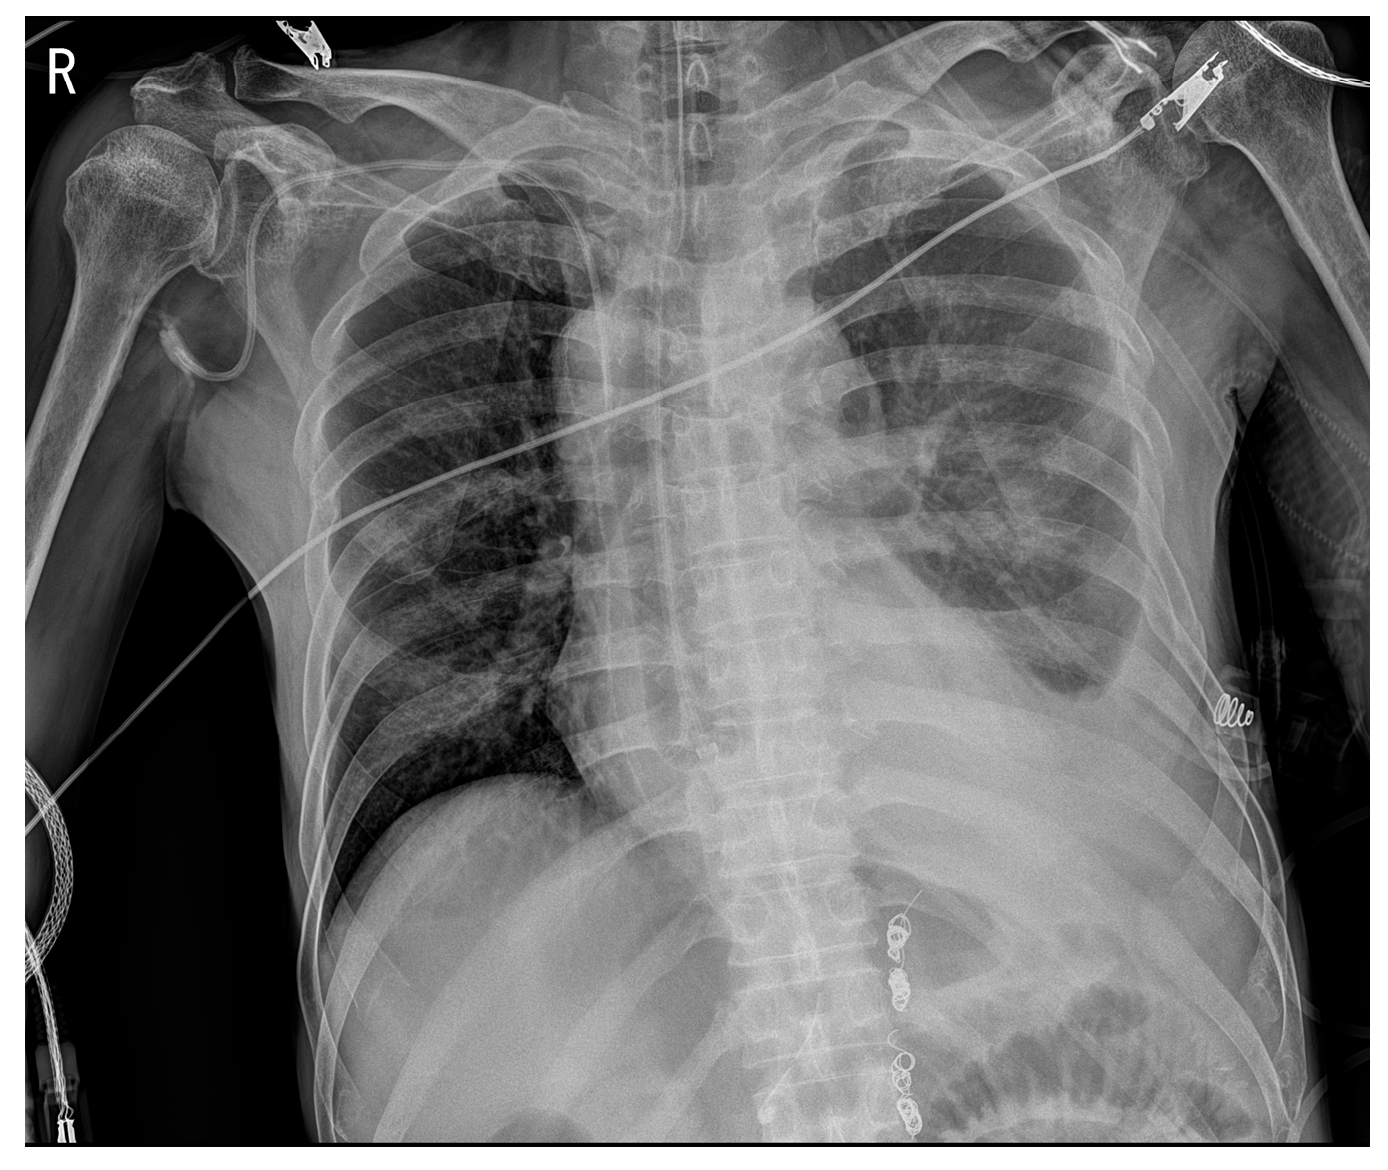

2. Case Presentation